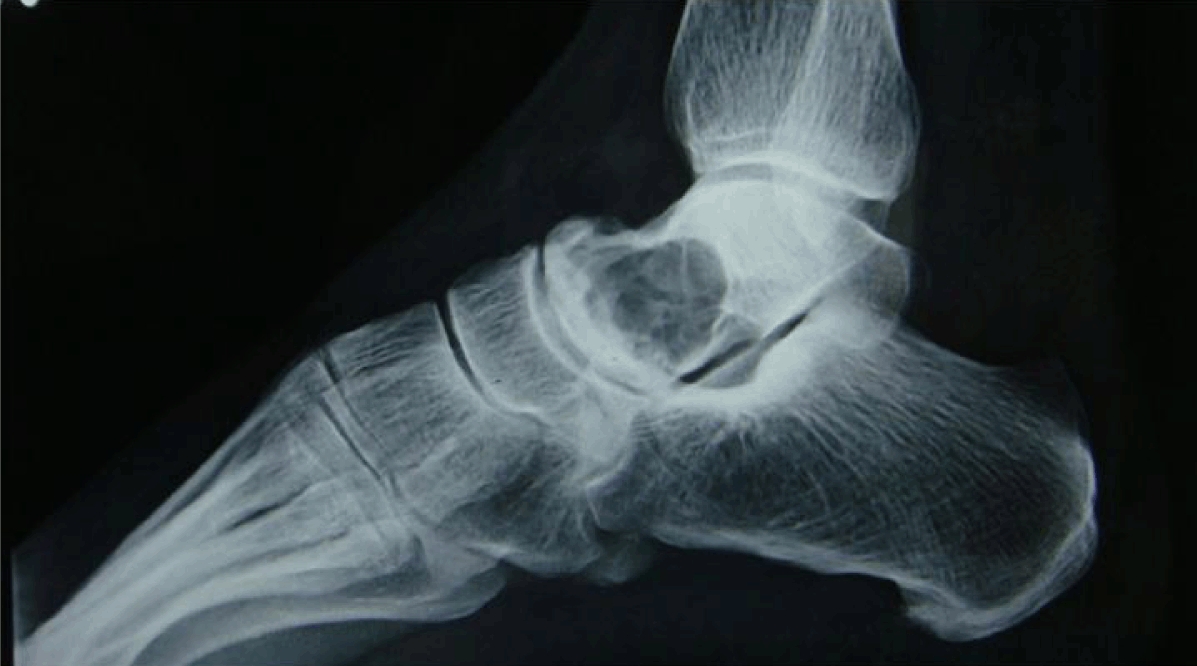

A 45-year-old female was admitted to the Medical College Hospital with complaints of pain in the right ankle since 6 years. On examination tenderness was present over the lateral aspect of right ankle. Plantar flexion was restricted. There was no distal neurological or vascular deficit and the regional lymphnodes were not palpable. X-ray findings of right talus showed a lytic, loculated appearance with prominent sclerosis of the edges of the lesion. There was no matrix mineralization. The zone of transition of the lesion was narrow. (Figure 1) Clinical diagnosis of osteoclastoma was made. Currettage and bone grafting were done. Currettage was sent for histopathological examination. The currettage was processed routinely. Hematoxylin and Eosin stained sections showed spindle cells arranged in storiform pattern with involvement of bone at the foci. The cells had elongated bland nuclei, moderate to abundant cytoplasm and indistinct cell margins. No pleomorphism and atypical mitotic figures were found. Scattered foamy histiocytes along with occasional foci of scattered osteoclast type of giant cells were found. (Figure 2) (Figure 3) The final diagnosis of benign fibrous histiocytoma was made. Patient's symptoms disappeared completely 10 days after operation. There was no evidence of recurrence after two year of postoperative follow-up.

Figure 1: Preoperative X-ray shows osteolytic lesion of talus.

There is no defined age group for this tumor except that patients are generally older than those found with a non-ossifying fibroma. Korhan et al., Zia et al. reported a case of 65 years and 32 years old female, respectively as in our case. [7] [8] It is usually found in long bones most commonly in the femur and tibia, but various authors reported BFH from pelvic, lumbar spine, rib. [8] Benign fibrous histiocytoma in the present case is unusually located in the talus. Most of the time tumor presents with pain at the site of lesion which is similar to our study. The diagnosis was based on X-ray findings, computed tomography (CT) scan, and magnetic resonance imaging (MRI) scan. In the present case only X-ray was done which showed osteolytic lesion of the talus. Benign fibrous histiocytoma should be differentiated from xanthoma of the bone, which radiologically resembles non-ossifying fibroma and osteoblastoma. Some consider these lesions as neoplastic processes under the broad category of BFH,where as others consider primary xanthoma of bone as a separate entity. [9]